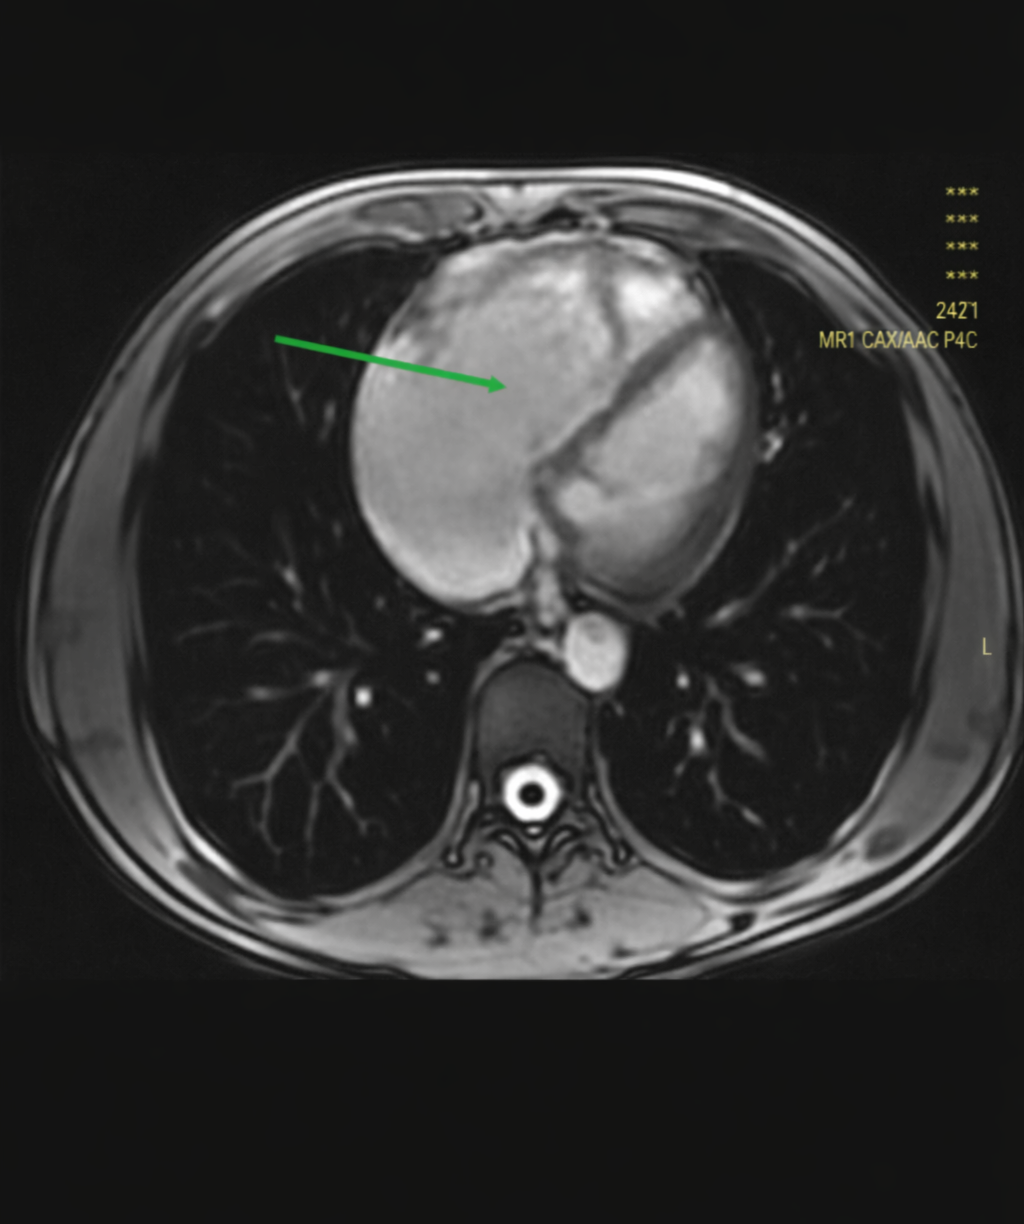

Figure 2: CMR-axial scout cine image of the chest shows markedly dilated right heart chamber as indicated by the solid arrow

CMR (Figure 2) showed diffuse RV wall hypokinesis, mild RV apex dyskinesia with right ventricular ejection fraction (RVEF) 43%. The RV was dilated and hypertrophied; the ratio of RV end diastolic volume to body surface area (RV-EDV/BSA) was 125 milliliters/meter square. Fibro fatty infiltration or late gadolinium enhancement (LGE) was not seen during the study. LVEF was 50%; interventricular septal thickness was normal.